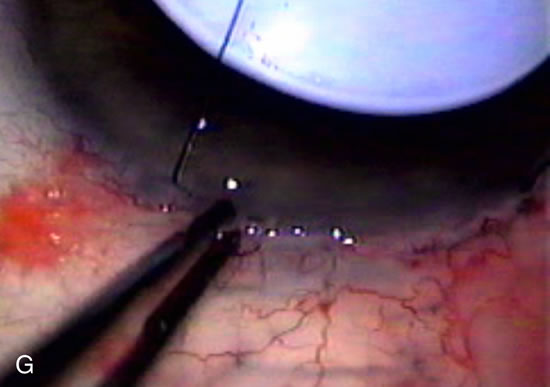

Fig. 8. Bleb appearance after limbus-based versus fornix-based conjunctival flaps. Even though the IOP is thought to be equivalent between limbus and fornix-based conjunctival flaps, the final bleb appearance varies considerably. A. During a limbus-based approach, an incision through conjunctiva 10 mm posterior to limbus will sever through multiple arterial vessels, increasing the likelihood of an avascular bleb. B. The tissues are dissected down to the sclera further cutting feeder vessels from Tenon's capsule. C. The wound is closed inciting a cascade of wound healing events that may ultimately lead to scarring producing a barrier to aqueous flow. D. This leads to walling off of a bleb that has lost some of its overlying vascularity (pale cystic avascular bleb). E. During a fornix-based conjunctival approach, the incision is made at the limbus and tissues undermined. F. The incision is closed at the limbus; no conjunctival vessels are severed over the bleb area. G. This fosters the formation of a shallow diffuse pale bleb with a normal vessel pattern.

During preoperative slit-lamp biomicroscopy, the surgeon evaluates the condition of the conjunctiva and decides on a fornix-based or a limbus-based conjunctival approach.174–177 There are definite advantages and disadvantages of each approach (Table 3). With proper wound construction, there appears to be very little difference in long-term IOP control between the two incisional groups. However, the long-term bleb appearance varies considerably between the two incisional groups,178 with a limbus-based conjunctival flap more likely to develop a cystic bleb especially if an antimetabolite is used179 (Fig. 8).